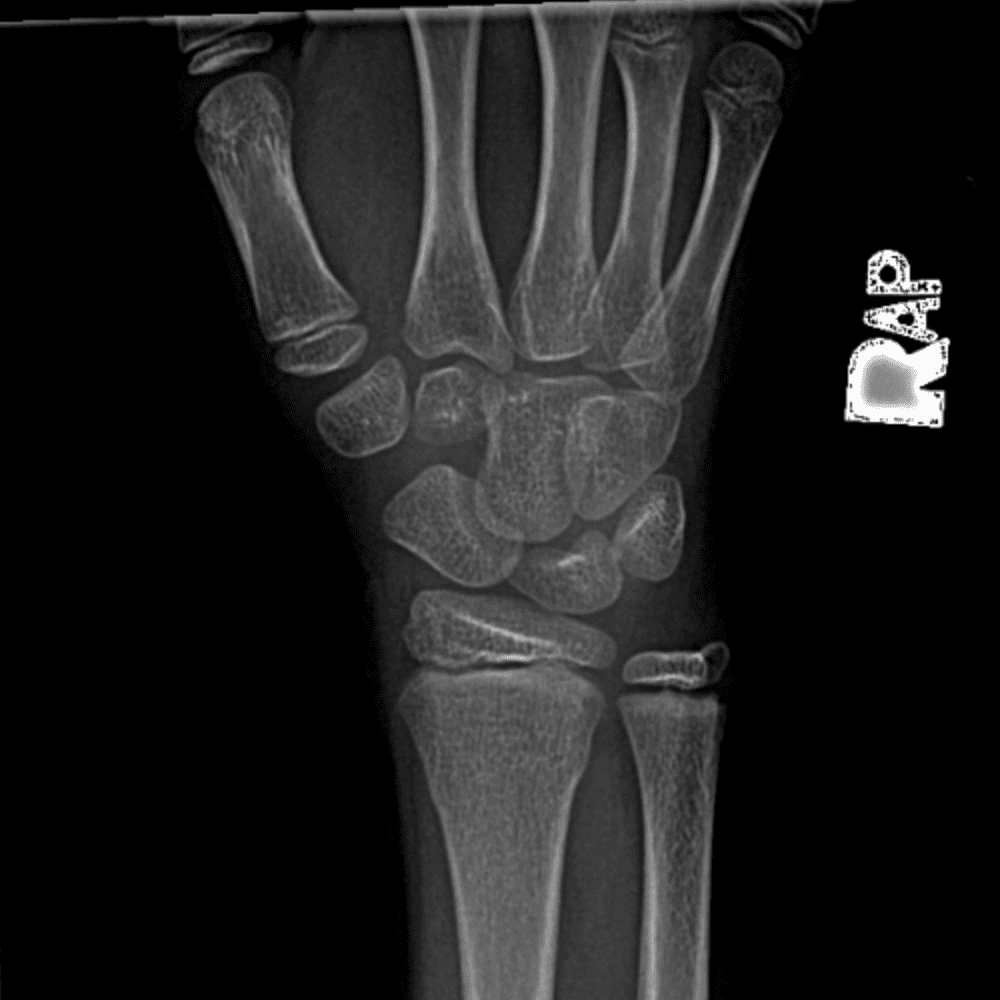

Simulates call by including subtle or difficult cases and some normals.

30 cases